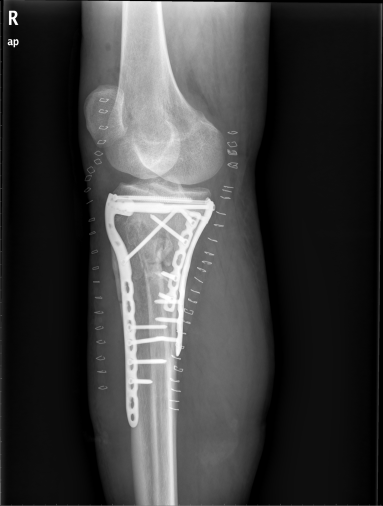

骨折是我们在日常生活中常见的一种疾病,通过手术治疗往往可以达到稳定的固定作用。手术固然重要,但术后功能康复亦不能忽视。小编最近就遇到一位胫骨平台骨折患者,该患者在4个月前发生了车祸导致胫骨平台骨折,并进行切开复位内固定手术治疗。但由于在术后一直畏痛少动,未进行积极地康复治疗,致使患侧膝关节难以像健侧一样伸直,下肢功能急剧下降。为了避免出现以上情况,今天小编就与您分享,胫骨平台骨折术后该如何正确康复。

胫骨平台是膝关节重要的负荷组成部分,也是膝关节创伤中最常见的骨折之一,多发生于强烈的外翻和内翻应力合并轴向载荷时,同时股骨髁对其下胫骨平台有压力和剪切力,可造成劈裂骨折、塌陷骨折或两者兼有。当发生胫骨平台骨折后,需要通过手术切开复位固定,术后要及时进行康复训练,以加快骨折愈合,促进患肢功能恢复。

1. 拍摄膝关节X光片复查,并根据骨折线愈合情况及专业医生建议决定是否开始进行患肢负重练习。